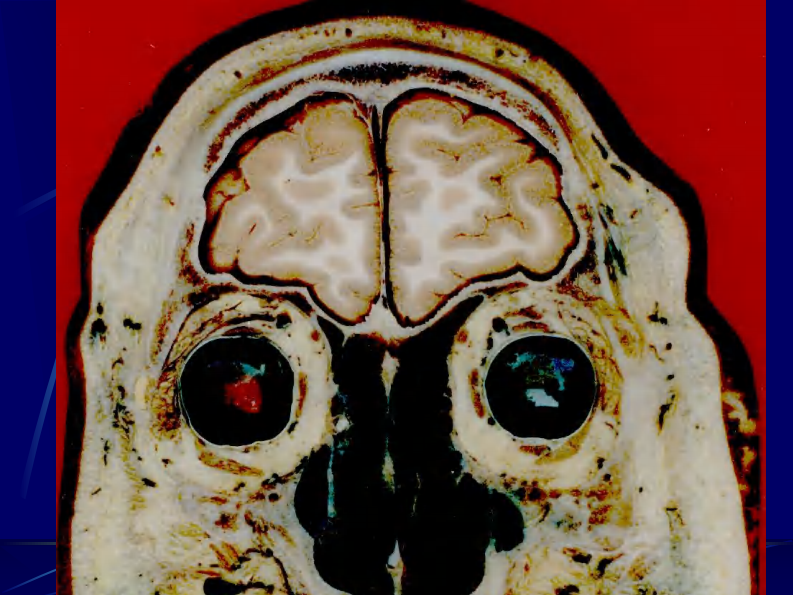

04 头部连续冠状断层解剖及MRI.pdf